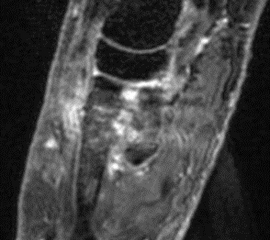

Abbildung 3.3.a und b: Patient mit rezidivierenden Schmerzen, zeitweise auch Schwellung und Überwärmung im linken Vorfuß (medialseitig auf Höhe der Fußwurzel/Mittelfußknochen) seit einem Umknicktrauma vor 4 Jahren. Nativradiologisch unauffällig. Das MRT zeigte eine Ruptur des Ligamentum fibulotalare anterius sowie einen knöchernen Ausriss aus der distalen Fibula; zusätzlich Verdacht auf Sinus tarsi Syndrom bei einem Ganglion medial am unteren Sprunggelenk. Die SPECT/CT zeigte eine Stressreaktion am Ansatz der Tibialis-posterior-Sehne des linken Fußes bei einem Os naviculare Typ III, was mit dem klinischen Befund korrelierte. Das MRT wies in diesem Bereich keine wegweisenden Signalveränderungen auf (Abbildung 3.3.a); im SPECT/CT eindeutig erhöhter Metabolismus ohne weitere Auffälligkeiten (Abbildung 3.3.b).

Zum Lesen der Bildbeschreibung und zur Vollansicht bitte die Bilder anklicken. Bilder: H. C. Rischke